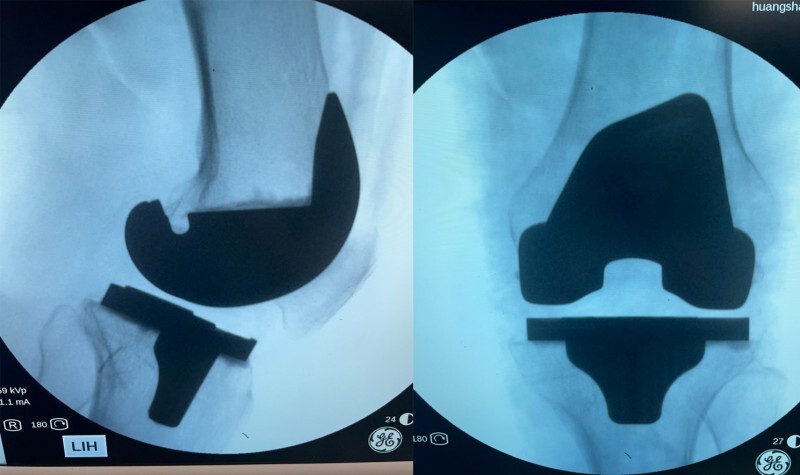

第2例:机器人辅助下全髋关节置换术

歙县人江某某,81岁,一周前在家中不慎摔倒后疼痛不已,被家人送来黄山新晨医院就诊,经过仔细检查后确认为“左股骨颈骨折”入院。

考虑到患者年龄较大,且基础疾病较多,骨科团队经过周密考虑讨论之后,建议其家属考虑机器人手术,在仔细了解手术机器人的相关知识后,其家属欣然接受,并表示江老先生很幸运,赶上了好机会。手术历经两个小时左右顺利结束,目前江老先生各项情况良好。